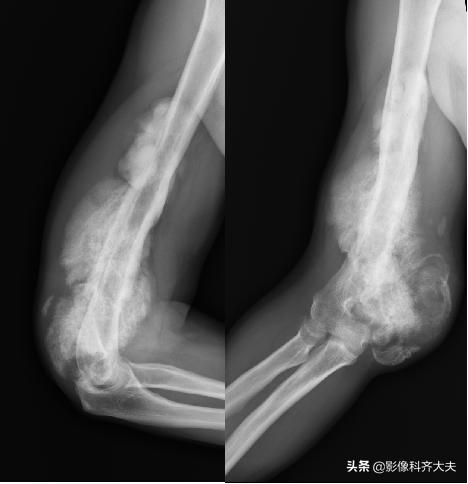

肱骨远端骨折后大量骨痂形成,骨小梁穿越骨折处